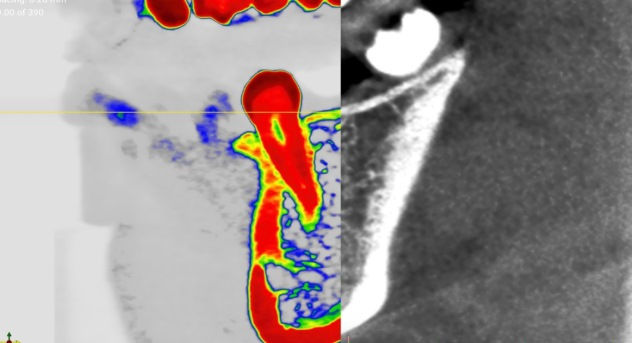

SIMDENSITY uses standard imaging data from computed tomography (CBCT), providing doctors with previously unattainable knowledge about the bone density of the jaw and mandible. As a result, doctors can make more informed decisions regarding implant placement procedures.

Relying on AI technology and computerized image analytics, SIMDENSITY offers a calibrated measurement of bone density in absolute units of g/cm³. Doctors receive a tool that enables precise treatment planning and surgical navigation. The system, operating in a cloud model (SaaS), is the first in the world to allow non-invasive measurement of bone tissue density in the planning stage of implantation procedures.